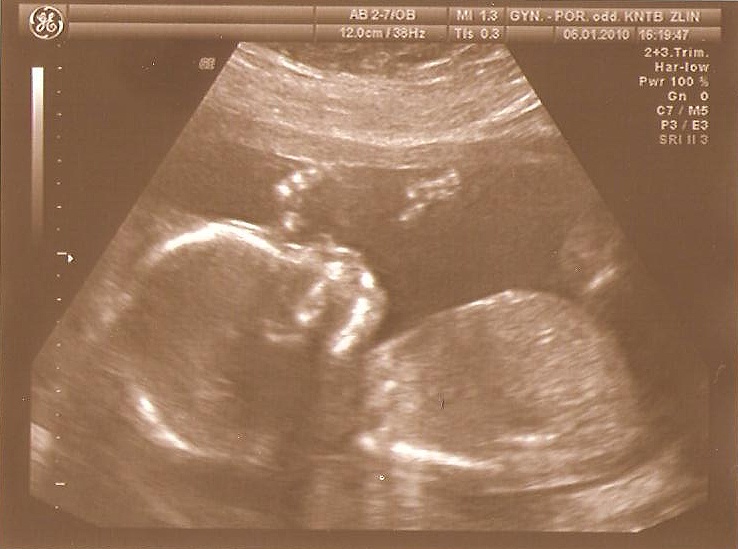

09-18+4tt, NT screening II.trimestru